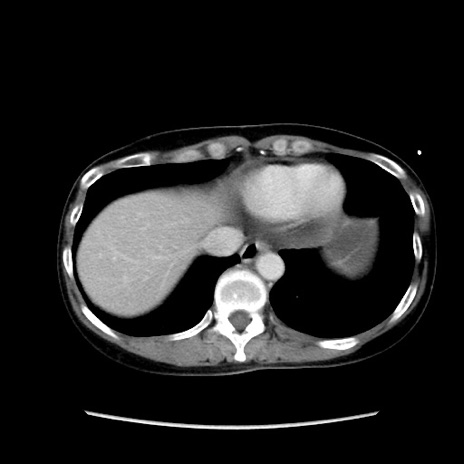

冠状断像

【症例】40歳代 女性

【主訴】上腹部痛、嘔気・嘔吐

【現病歴】約9時間前頃から急に上腹部痛、嘔気、嘔吐が出現。改善しないため救急要請。

【既往歴】子宮頚癌(広汎子宮全摘術、放射線療法)、腸閉塞